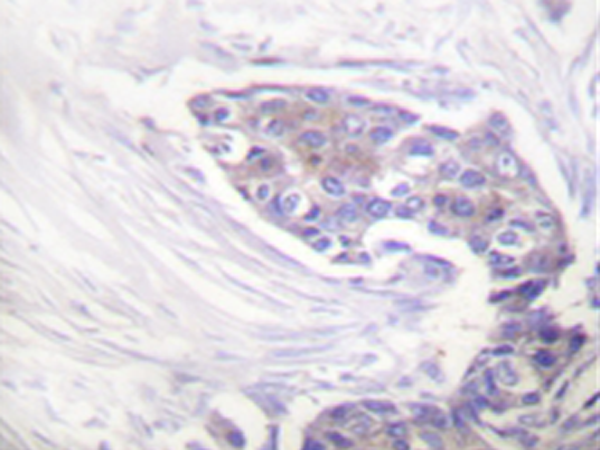

IHC positive control: |

Human breast carcinoma tissue |

IHC Recommend dilution: |

50-100 |